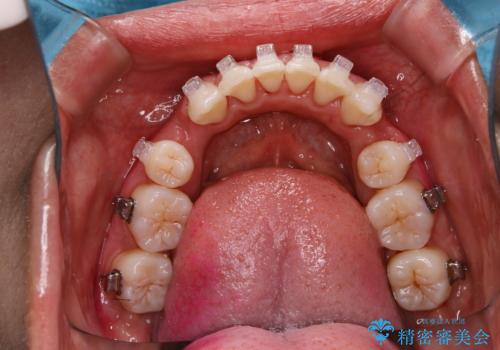

エアフロー60分コースを行い、装置周りや全体の汚れを徹底的に除去しました。

矯正治療中も清潔な口腔内を保つことは、とても大切です。そのため、定期的に専門的な機械・材料を使用したクリーニングを行うことがおススメです。